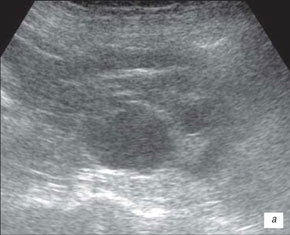

Ехограма розширення порожнинної системи нирки

А – розширення сечоводу:

Б – на тлі сечового міхура.

1 – сечовий міхур, 2 – сечовід

На даній ехограмі спостерігається: зменшення розмірів нирки на стороні поразки; циклічна зміна діаметру сечоводу у верхньому і нижньому відділах; вертикальну спрямованість сечовідно-міхурного викиду, який в нормі має напрям під кутом 30–40° по відношенню до умовної лінії, що сполучає гирла сечоводів.